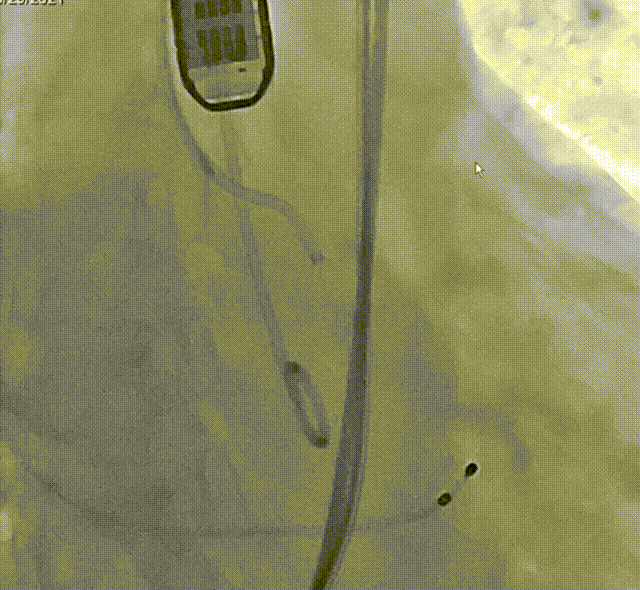

术后造影

术后即刻评估

术后即刻跨瓣压差

对本例手术,罗建方教授团队通过术前详尽的检查分析评估,对可能发生的各种突发情况进行充分预估,并准备了相应的应对预案,手术中采用左右重叠体位,标准位释放,术后跨瓣压差降至0mmHg,血流动力学得到有效改善,为患者带来更长久的生存预期和更高的生活质量。本例手术的成功开展再次展现了罗建方教授团队在诊治高难度复杂主动脉瓣膜疾病的雄厚实力和丰富经验,也为临床上心室腔小、心肌肥厚、横位心的Type1型二叶瓣患者行TAVR治疗提供了更多的参考。